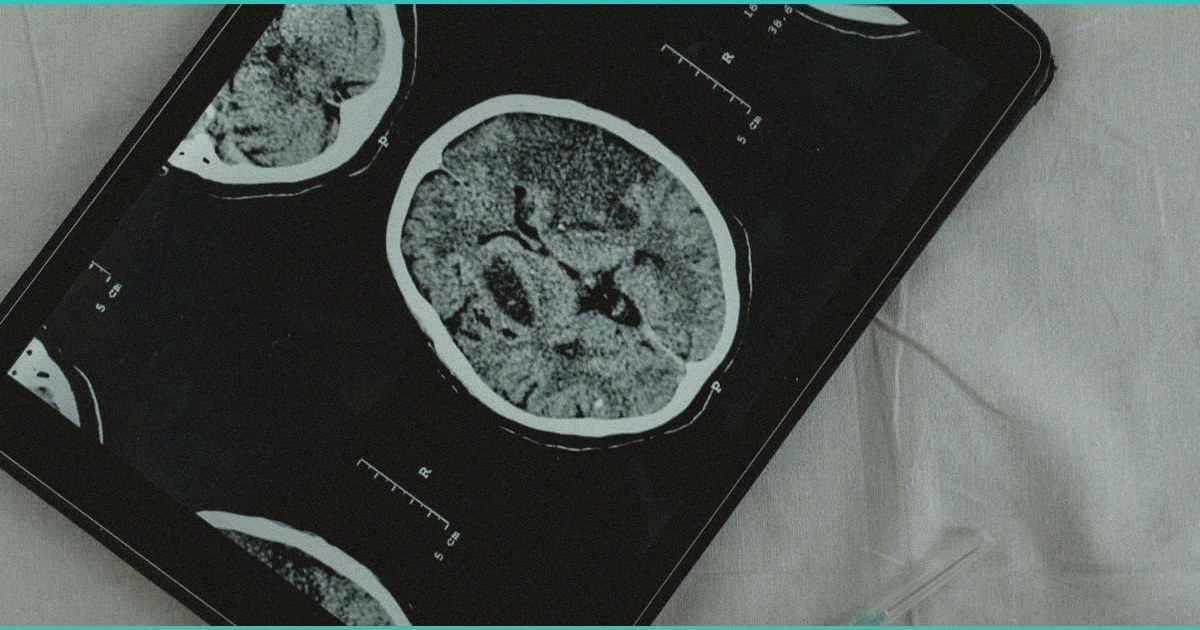

A study out of Sweden received wide coverage this cycle, demonstrating that teen cannabis use follows the same population-level consumption distribution as alcohol — meaning when average use rises, heavy use rises disproportionately among the most vulnerable youth. Separately, research highlighted in Medscape linked adolescent cannabis use to increased risk for serious psychiatric conditions including psychotic and bipolar spectrum disorders, while additional reporting explored the association between early use and broader psychiatric diagnoses. The clinical throughline is consistent: the developing brain is uniquely sensitive to exogenous cannabinoids during synaptic pruning and neural circuit maturation, and age of initiation remains one of the most modifiable risk factors. For parents and clinicians, the takeaway is that community-wide prevention strategies and honest household conversations matter as much as individual screening — and that delaying use until the mid-20s is the single strongest harm reduction lever we have.